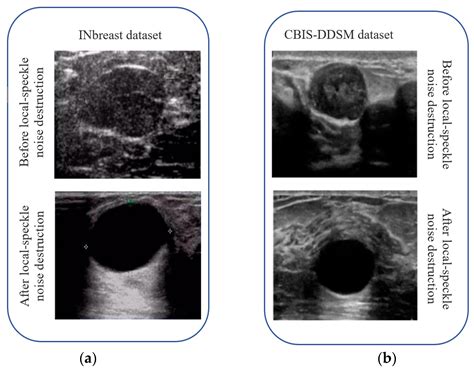

• Speckle Noise: Common in radar and ultrasound images, speckle noise appears as a granular pattern that can obscure fine details.

In medical imaging, reducing noise in the image is crucial for accurate diagnosis. Techniques like bilateral filtering and machine learning algorithms are often employed to enhance the clarity of medical images, such as MRI and CT scans. These methods help radiologists detect subtle abnormalities that might otherwise be obscured by noise.